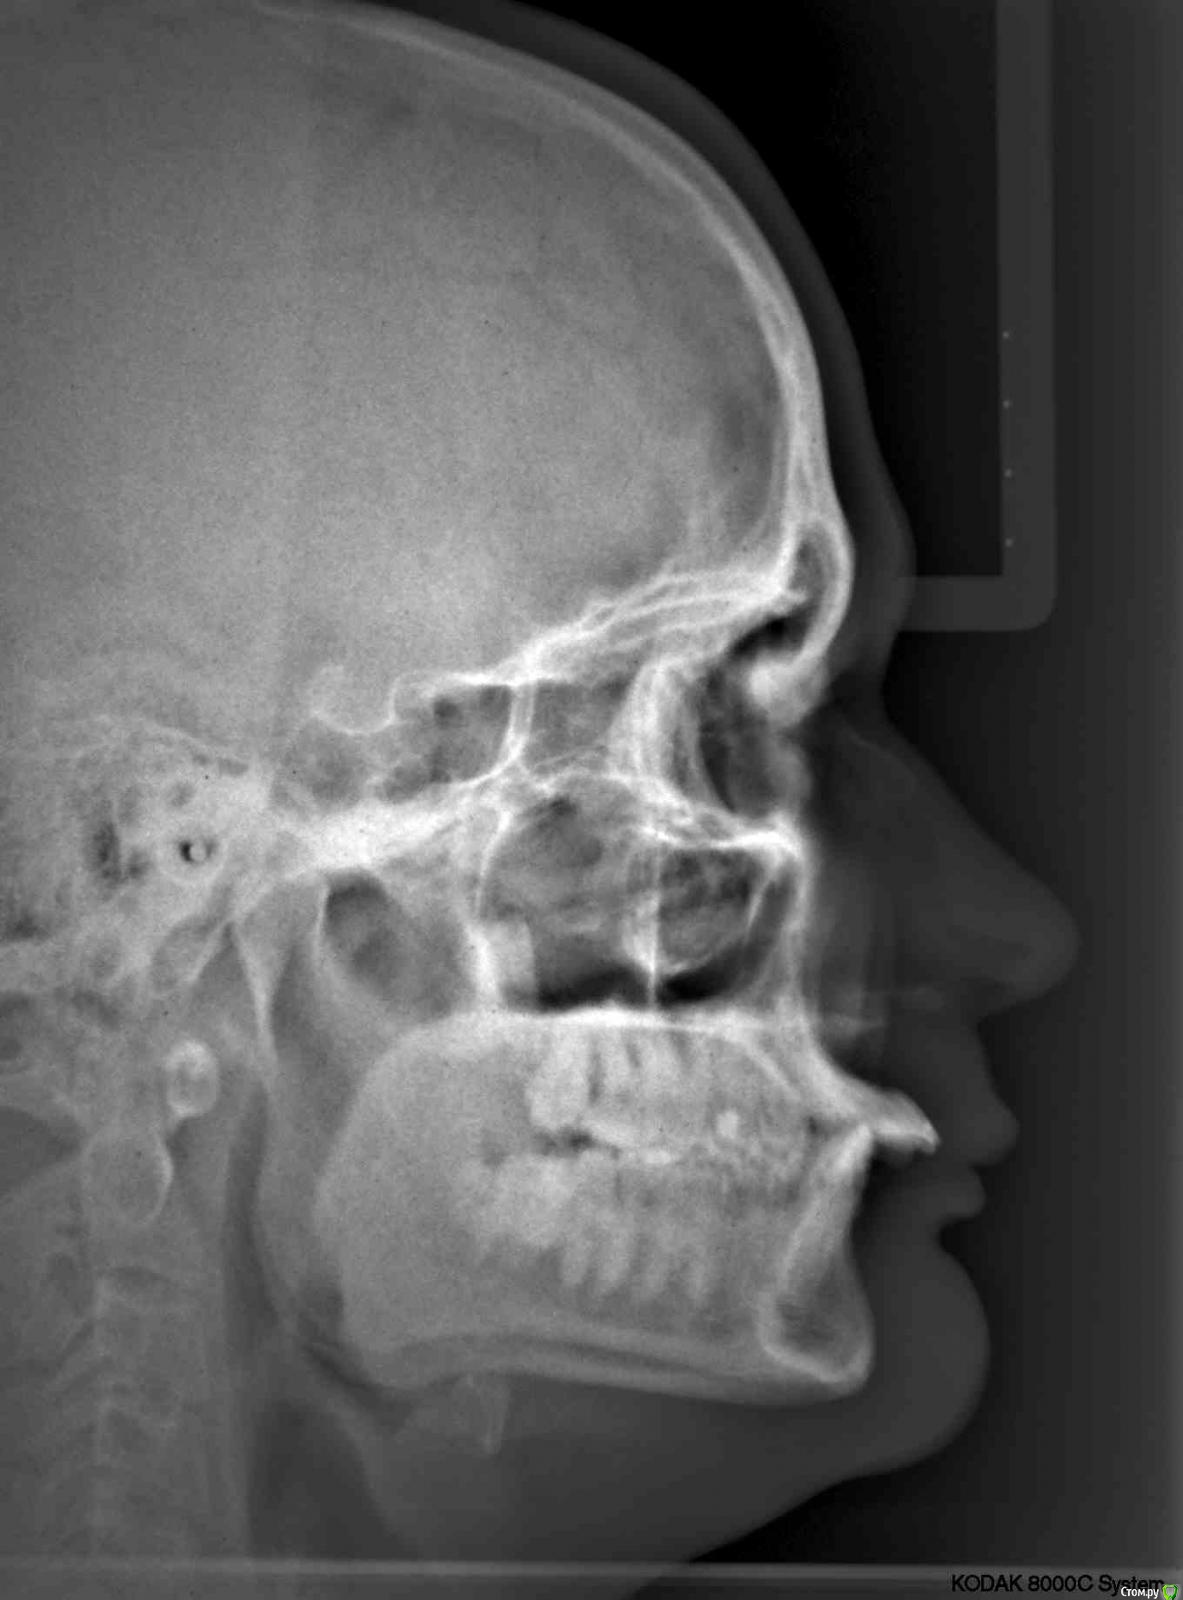

kozloff Опубликовано 15 ноября, 2015 Поделиться Опубликовано 15 ноября, 2015 Да, нужно исключить синусит.А еще можно заподозрить дисфункцию ВНЧС, на вашем снимке (ОПТГ) вызвает опасение расположение суставных головок. Но это может быть дефект снимка.Обязательно сделайте КТ, на одном снимке можно и пазухи рассмотреть, и ВНЧС. Ссылка на комментарий

Jurai Опубликовано 22 ноября, 2015 Поделиться Опубликовано 22 ноября, 2015 Есть проблема во фронтальном участке верхней челюсти: общая убыль костной ткани, ячеистая структура кости. смещение зубов так, что корни изогнулись, это значит, что либо резорбция (рассасывание) либо очень длительное уже идет воздействие. Могу подозревать новооборазование в этом участке.Вам нужна консультация челюстно-лицевого хирурга-онколога. 1 Ссылка на комментарий